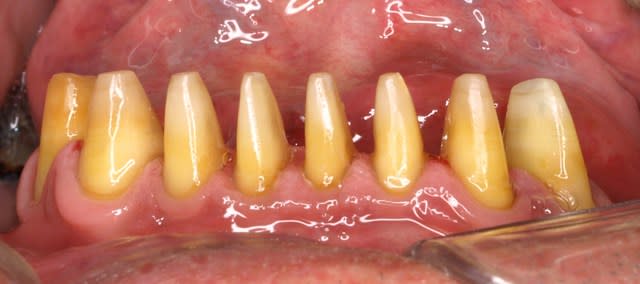

pour revenir a l aspect poli,

ç'est pour moi la seule façon de verifier les axes des tailles.

les reflets te guident au fur et a mesure de la taille.ç'est bonnard dans les cas de bridges.

belles tailles ! , il me semble que les dents sont vivantes, elles sont préparées pour raison esthétique ?

@Azerty

non,non toutes devitalisées pour raison endo paro.il ne restait que 3mn max d os par dent (incisives).il fallait les tenir pendant la taille de peur qu elles tournent sur elles meme!!

Non non y a rien qui fâche,on parle bien du cas de la photo des dent du haut ??

c est un cas d occluso ou j ai du tailler toutes les dents du haut et toutes les dents du bas (sauf 1 en bas parce que sans antagoniste ),

toutes en @max +bridge zircon antérieur,+1 ou 2 facettes.

En fait suite a un ancien bridge antérieur du haut avec des cingulums trop gros et rectilignes

et des ccm a la con en bas

il a declanché une para-fonction et a tout usé.De plus il y avait un décalage dans le sens sagittal et une absence de décalage entre oim et centrée.Ce cas là ne pouvais pas se corriger avec de l adhésive .

ben j ai deja repondu a la question!!!:

"@Azerty

non,non toutes devitalisées pour raison endo paro.il ne restait que 3mn max d os par dent (incisives).il fallait les tenir pendant la taille de peur qu elles tournent sur elles meme!!"

les dents n avaient rien.le ttt classique etait extraction des 4 incisives et rajout sur le stellite .J ai preferé un bridge de contention en fonction du stellite existant